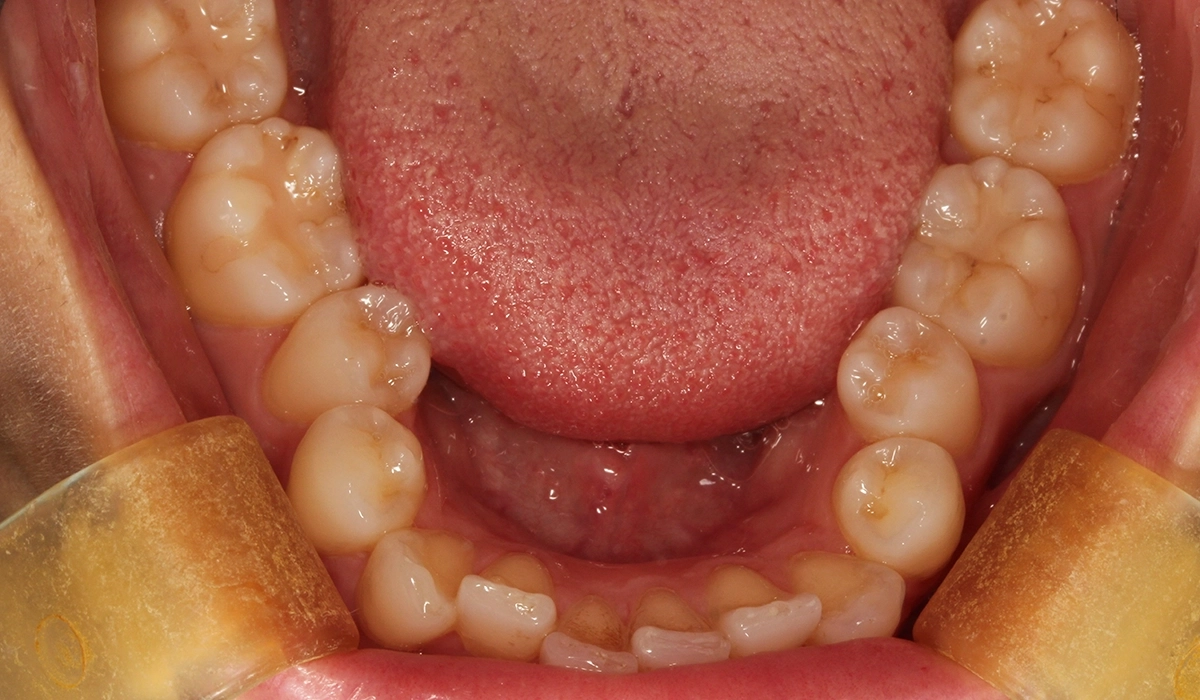

術前:上顎

術前:下顎